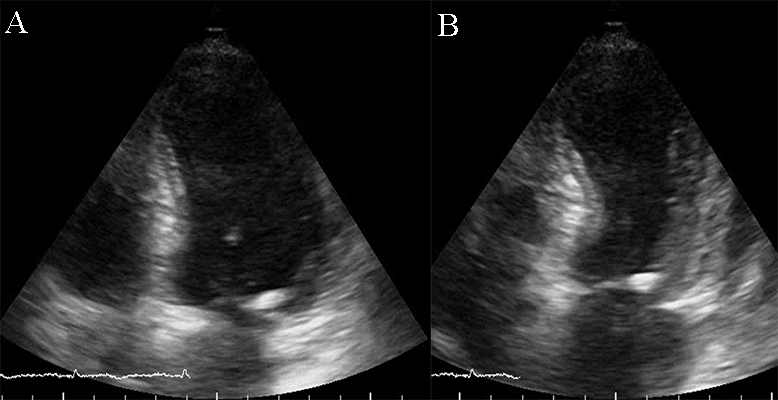

The causes of RCM can be classified as non-infiltrative (familial) or infiltrative (storage diseases), but the same pattern can be found in other disorders like diabetic cardiomyopathy, scleroderma, and endomyocardial fibrosis [38, 39, 40]. An accurate myocardial investigation by MRI and myocardial scintigraphy allows the diagnosis of different types of myocardial amyloidosis which is increasingly observed in the elderly either by transthyretin (aTTR) or by AL–light immunoglobulin chains in different plasmacytomas [41]. Another type of RCM is found in sarcoidosis and it can cause global or regional LV wall motion abnormalities. In some cases, the changes are specifically revealed on the basal posterior and lateral wall of the LV [42, 43, 44]. The most common finding is myocardial thinning, but RCM can also present with hypertrophy or it can include myocardial aneurysms [38, 45, 46, 47]. In some RCMs such as endomyocardial fibrosis or hypereosinophilic syndrome apical intraventricular thrombosis may be recognized; this may be responsible for pulmonary or systemic cardioembolism [48]. In RCM due to amyloidosis, apart from hypertrophy and wall motion abnormalities (Fig. 9), valvular involvement may also be noted with thickened aortic cusps or mitral leaflets determined by local deposition of amyloid [49].

Fig. 9.The echocardiographic aspect of cardiac amyloidosis, associated with aortic stenosis. (A) short-axis view, showing left ventricular hypertrophy. (B) Speckle tracking echocardiography obtained by measuring longitudinal strain in apical 4 chamber view, shows a significantly reduced GLS (global longitudinal strain) of –8.6%.

2D echocardiography, as mentioned before, highlights a low or normal diastolic volume of the LV associated with normal or only mildly reduced LV ejection fraction, as criteria for RCM. Also, one or both atrial enlargement is identified, with increased pressures, and normal pericardium. Once the typical pattern of RCM is identified, the echocardiogram can reveal also some features for a specific etiology. For example, in cardiac amyloidosis, the left and right ventricular walls are often mildly and symmetrically thickened, the myocardium may have a granular appearance, and myocardial strain imaging may show preserved apical function. However, it is not sufficient information neither to confirm, nor exclude cardiac amyloidosis [39, 40, 50], and further testing is needed. Moreover, in sarcoidosis global or regional (typically basal posterior and lateral) LV wall motion abnormalities may be observed. The most common finding is myocardial thinning, while less common findings include myocardial aneurysms, hypertrophy, and pericardial effusion [51, 52]. In eosinophilic inflammation of the myocardium or hypereosinophilic syndrome, the echocardiogram is often unrevealing during the initial necrotic stage. In the thrombotic stage of the disease, the damaged endocardium may have associated thrombus, predominantly involving the ventricular apex [3, 5, 38, 52, 53]. During the last, fibrotic stage, increased endomyocardial echogenicity is seen, affecting one or both ventricles, sometimes with overlying thrombus; the ventricular filling can be restricted, and atrioventricular valve leaflets may be tethered [53, 54, 55]. A pattern similar to hypereosinophilic syndrome can emerge in endomyocardial fibrosis. It may be characterized by LV, RV, or biventricular apical fibrosis [53, 54, 55]. In radiation-induced RCM the echocardiogram may show structural abnormalities within the field of radiation, such as calcified heart valves, a thickened pericardium, or focal wall motion abnormalities related or not to radiation-associated coronary artery disease [40, 42, 56, 57].